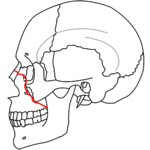

- Le Fort I fracture (horizontal), otherwise known as a floating palate, may result from a force of injury directed low on the maxillary alveolar rim, or upper dental row, in a downward direction. The key component of these fractures, in addition to pterygoid plate involvement, is involvement of the lateral bony margin of the nasal opening. They also involve the medial and lateral buttresses, or walls, of the maxillary sinus, traveling through the face just above the alveolar ridge of the upper dental row. At the midline, the inferior nasal septum is involved. Historically, it has also been referred to as a Guérin fracture, although this name is less commonly used in practice.

- Le Fort II fracture (pyramidal) may result from a blow to the lower or mid maxilla. The key component of these fractures beyond the pterygoid plate fractures is involvement of inferior orbital rim. When viewed from the front, the fracture is classically shaped like a pyramid. It extends from the nasal bridge at or below the nasofrontal suture through the superior medial wall of the maxilla, inferolaterally through the lacrimal bones which contain the tear ducts, and inferior orbital floor through or near the infraorbital foramen.